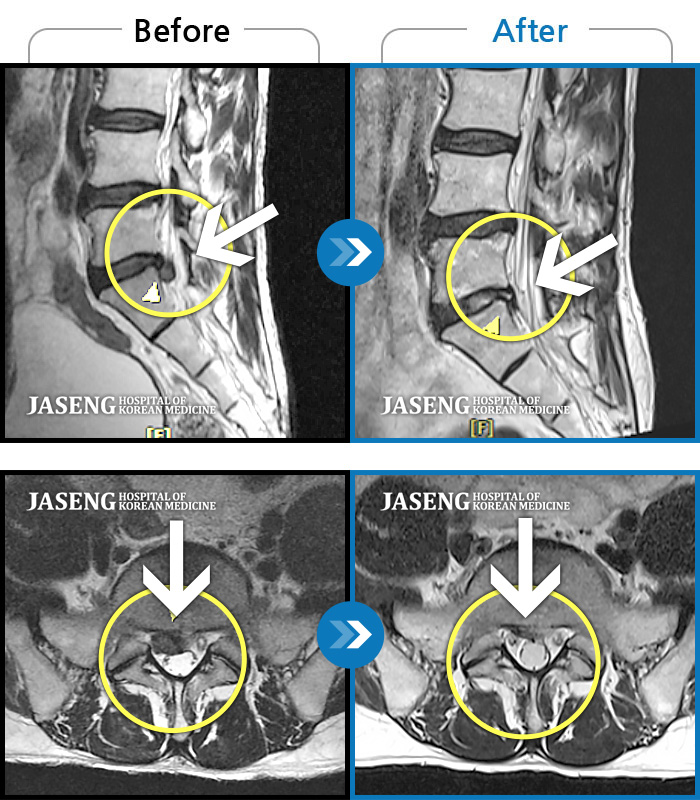

Before

After

허리 양측 통증, 서있을 때 찌르는 듯한 증상

2016.01.17 ~ 2019.04.19